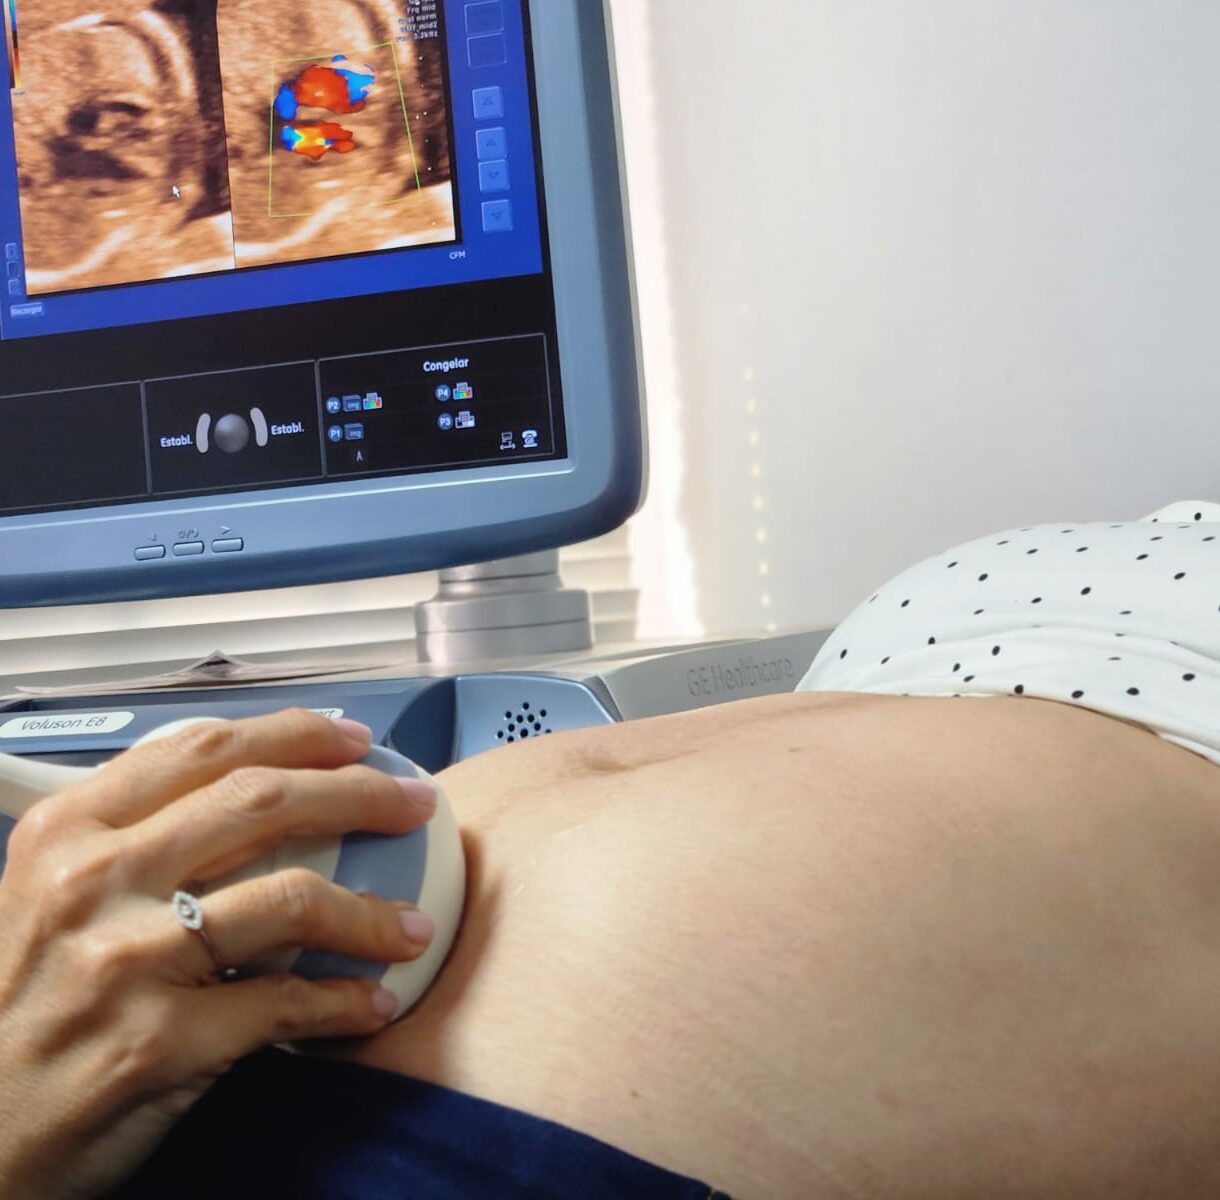

Tecnología avanzada

Disponemos de equipos de última generación para un diagnóstico preciso